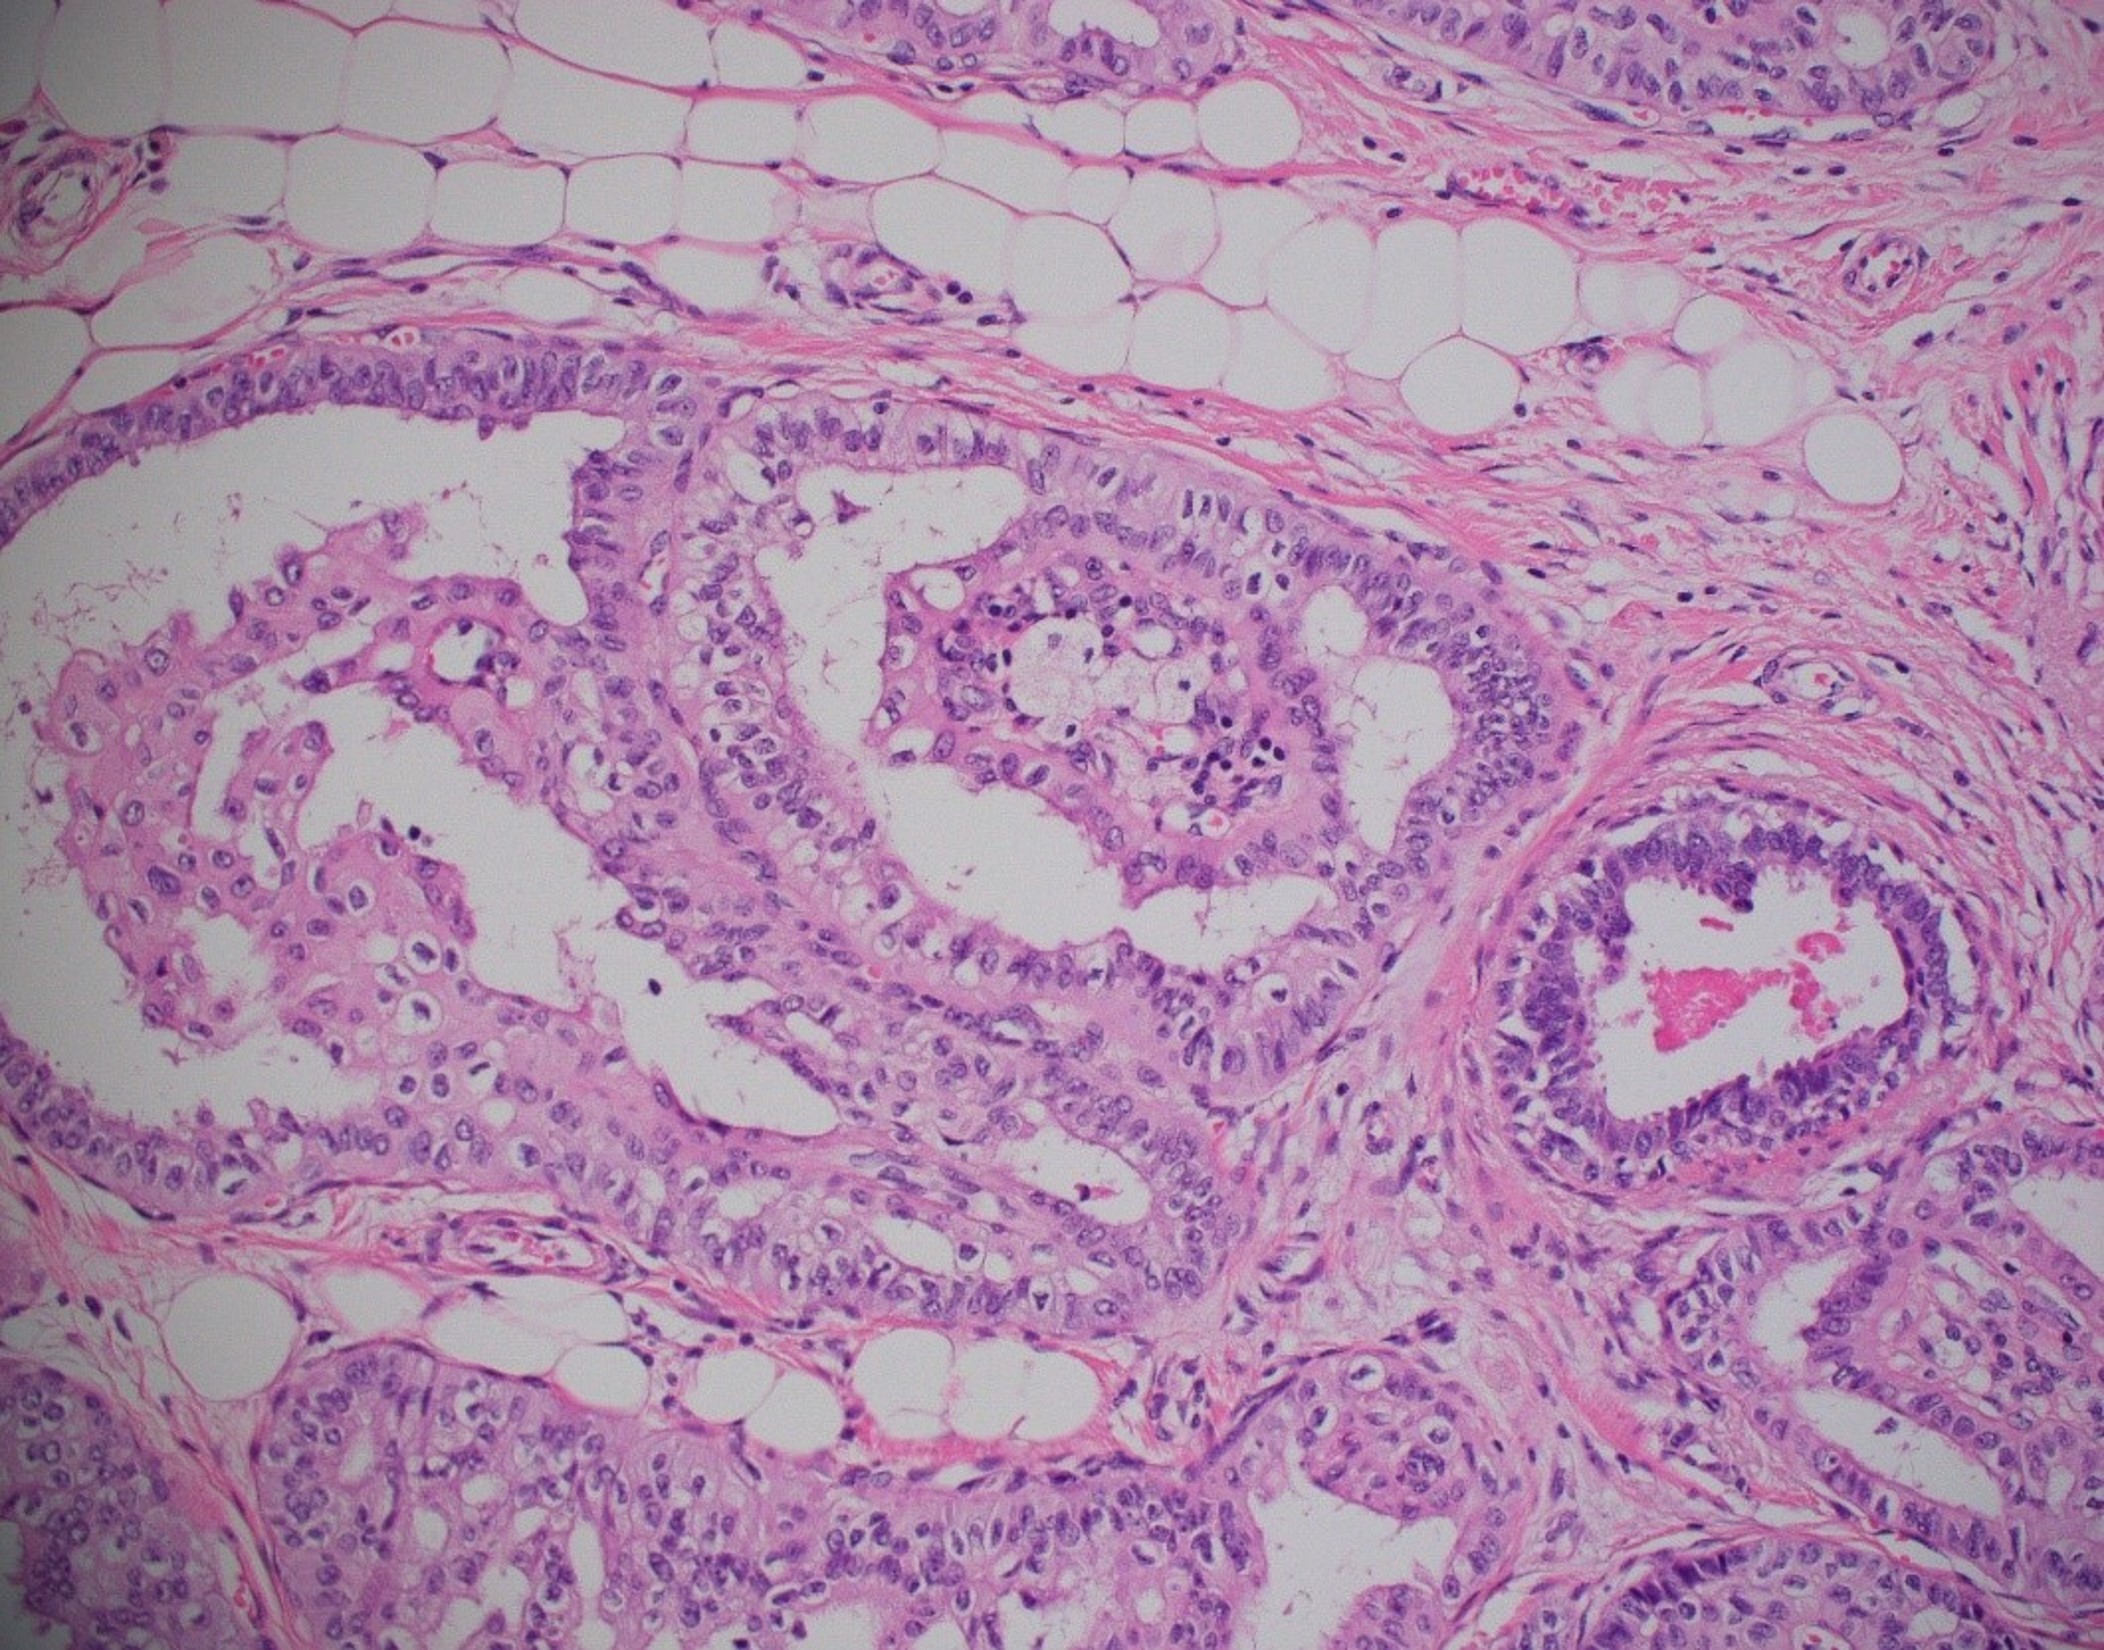

Morphologic Features

- Circumscribed nests of cells, many of which have fibrovascular cores. Foamy histiocytes are often present within the fibrovascular cores.

- Occasionally true papillae and cyst-like structures with colloid-like material are identified.

- Epithelial cells are tall, may have nuclear grooves and intranuclear cytoplasmic inclusions.

- The most characteristic feature is the presence of nuclei in the apical rather than basal pole of the cells hence the “reverse polarity”.

Breast tissue specimen containing tall cell carcinoma with reversed polarity. This tumor features solid nests of tumor cells with fibrovascular cores including foamy histiocytes (H&E stain, original magnification x20). Courtesy of H. Evin Gulbahce, University of Utah.